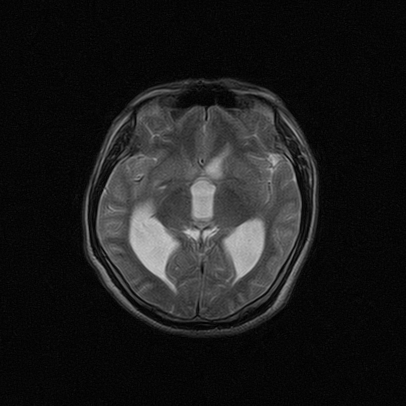

标题: MRI2064:少见病例。男性52,视力下降多年。 [打印本页]

标题: MRI2064:少见病例。男性52,视力下降多年。

四脑室区见混杂信号占位影,脑室系统扩张明显,临近结构显著受压称位,患者52岁,多考虑室管膜瘤可能性大

考虑第四脑室室管膜瘤并阻塞性脑积水。

考虑第四脑室室管膜瘤并梗阻性脑积水;部分性空蝶鞍;左侧上颌窦粘膜下囊肿。

考虑第四脑室室管膜瘤【血供丰富血管母细胞瘤可能】并梗阻性脑积水;部分性空蝶鞍;左侧上颌窦粘膜下囊肿。

比较典型的脉络丛乳头状瘤并脑积水,鉴别小脑蚓部血管母细胞瘤。